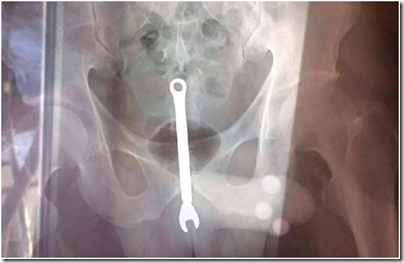

У автослесаря из Самары врачи дважды изымали из заднего прохода гаечный ключ

В Самаре у рабочего автослесарной мастерской, по его обращениям, дважды за несколько дней новогодних праздников врачи извлекали из заднего прохода гаечный ключ.

В первый раз врачи извлекли из прямой кишки гаечный ключ и не задавали вопросов, сообщил источник ИА Откровенно RU.

Через несколько дней бывший пациент вернулся с той же проблемой. Врачи потребовали объяснений. Мужчина сообщил, что гаечный ключ в его организм вставляют пьяные коллеги по автомастерской.